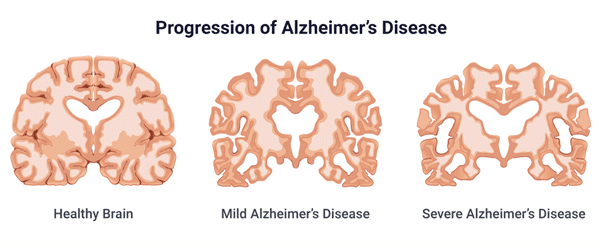

Despite this, the individual may experience memory lapses, such as forgetting familiar words or placing everyday objects. The progression to mild cognitive impairment can be predicted by increasing tau protein in CSF, right entorhinal cortex thickness, and right hippocampus volume on MRI.

Patients in this stage have severe memory and language impairment, such as anomia, paraphrasing errors, a decline in spontaneous verbal output, and a propensity for circumlocution to avoid forgotten words. Wandering in familiar settings and constructional apraxia result from impaired visuospatial ability.